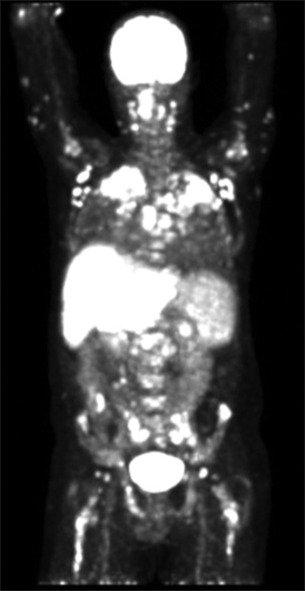

Sarcoidosis is a disease of unknown etiology, characterized by noncaseating granulomas. Generally, the condition primarily manifests in the lungs. Extrapulmonary involvement is common, but localization in the gastrointestinal system is rare. Here, we present the case of a 37-year-old male who became increasingly hemodynamically unstable during the diagnostic workup for sarcoidosis due to acute variceal bleeding. The underlying mechanism was later attributed to portal hypertension caused by hepatic involvement of the disease. This case demonstrates the importance of considering variceal hemorrhage as a rare but life-threatening complication of gastrointestinal localization of sarcoidosis.